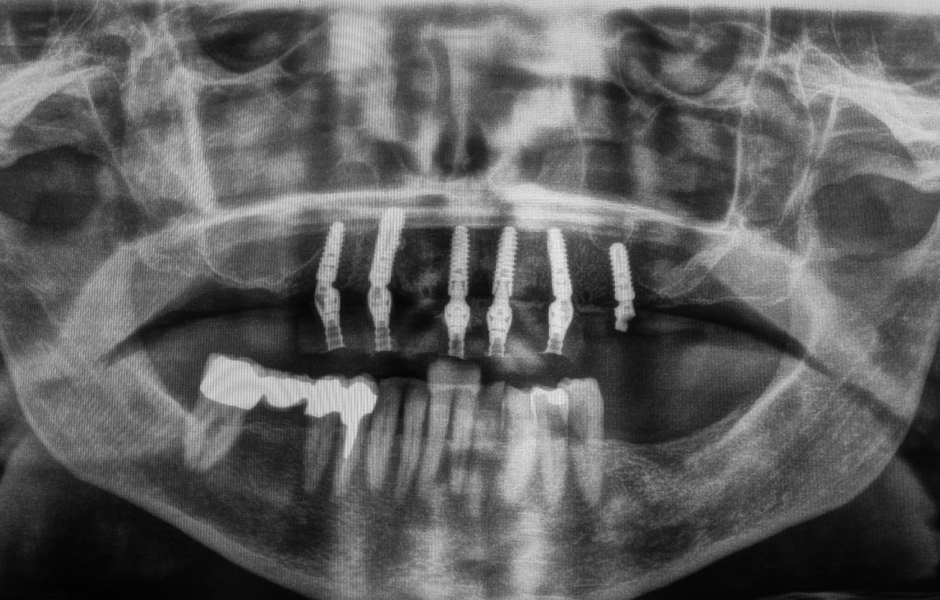

Bylo zavedeno šest implantátů copaSKY dle plánu – mírně palatinálně, aby se předešlo kontaktu s vestibulární kostní stěnou – v subkrestální poloze s primární stabilitou: v oblasti zubu 15: 3,5 × 10 mm, v oblasti 13: 4,0 × 14 mm, v oblastech 11, 21, 23: 3,5 × 12 mm a v oblasti 25: 4,0 × 10 mm.

RFA měření stability implantátů pomocí Penguin II (bredent medical) prokázalo vynikající hodnoty kolem ±75 ISQ, což potvrdilo vhodnost pro okamžité zatížení. Široce rozložený podpůrný polygon navíc poskytoval optimální stabilitu protetické konstrukce při současné ochraně tvrdých i měkkých tkání, nervů a cév.

Obr. 21: Rentgenový kontrolní snímek s protetickými kapnami.